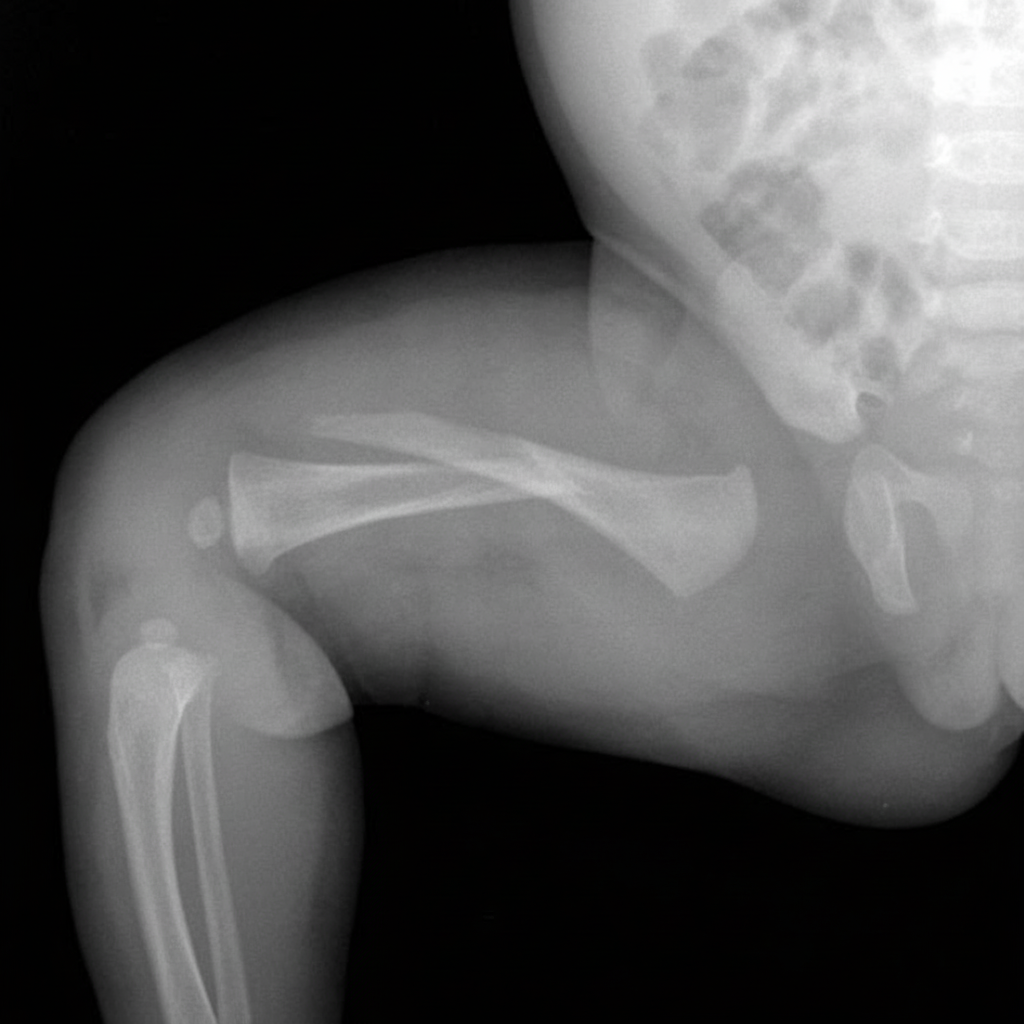

Which nerve is most at risk in the injury shown in the accompanying radiograph?

Explanation: ***Radial nerve*** - The **radial nerve** travels in the **spiral groove** (radial groove) on the posterior aspect of the mid-shaft humerus, making it highly vulnerable in **humeral shaft fractures**. - **Radial nerve palsy** presents with **wrist drop**, inability to extend the wrist and fingers at the metacarpophalangeal joints, and loss of sensation in the **first web space**. *Median nerve* - The **median nerve** runs medially in the arm and is protected from humeral shaft injuries by the **brachial artery** and surrounding soft tissues. - It is more commonly injured in **supracondylar fractures** or **carpal tunnel syndrome**, not mid-shaft humeral fractures. *Posterior interosseous nerve* - This is a **branch of the radial nerve** that passes around the **neck of the radius** and is at risk in **proximal radial fractures**. - It would not be directly affected by a **humeral shaft fracture** as it branches distally from the main radial nerve. *Ulnar nerve* - The **ulnar nerve** travels medially and posteriorly in the **cubital tunnel** at the elbow, making it susceptible to **medial epicondylar** or **olecranon fractures**. - It is anatomically distant from the **humeral shaft** and would not be injured in this fracture pattern.